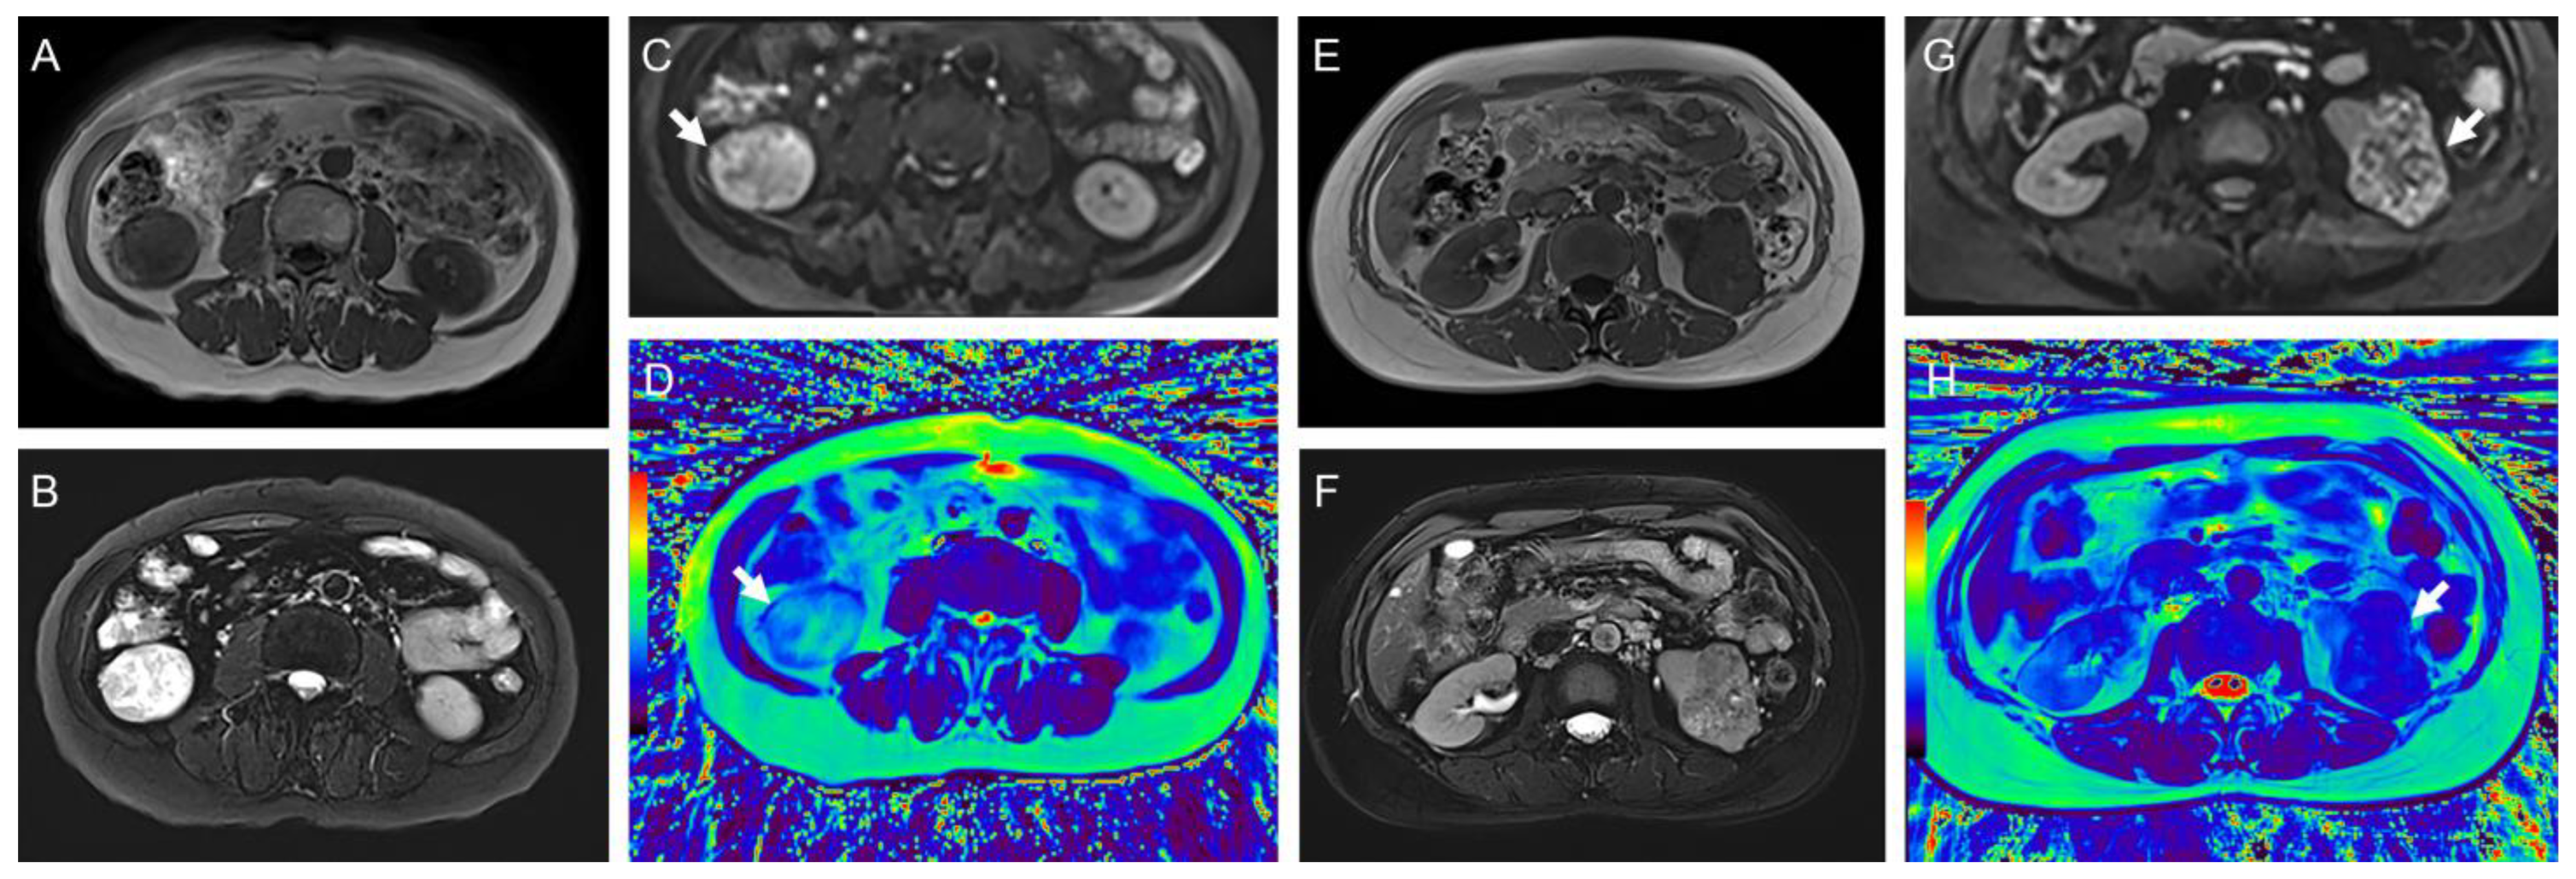

Figure 4. (AD) Representative images of a 44-year-old woman with minimal fat angiomyolipoma in the left kidney (arrow): (A) axial T1-weighted image; (B) T2-weighted image; (C) diffusion-weighted images (b = 800 s/mm2); (D) radial TSE T2 map. The mean ADC and T2 values of the tumor were 0.69 mm2/s and 82.2 ms, respectively. (EH) Representative images of a 44-year-old man with chromophobe RCC in the left kidney (arrow): (E) axial T1-weighted image; (F) T2-weighted image; (G) diffusion-weighted images (b = 800 s/mm2); (H) radial TSE T2 map. The mean ADC and T2 values of the tumor were 1.08 mm2/s and 116.0 ms, respectively. The color bar in the pseudocolor images (D and H) represents T2 values, which gradually increase from black to red.

The typical multiparameter MR images of different pathological types and WHO/ISUP grades are illustrated in Figure 3 and Figure 4, and the distribution of T2 and ADC values is provided in Table 3 and Figure 5.